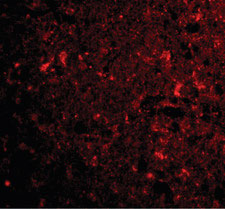

Immunofluorescence of CTRP4 in human brain tissue with CTRP4 antibody at 20 ug/ml.